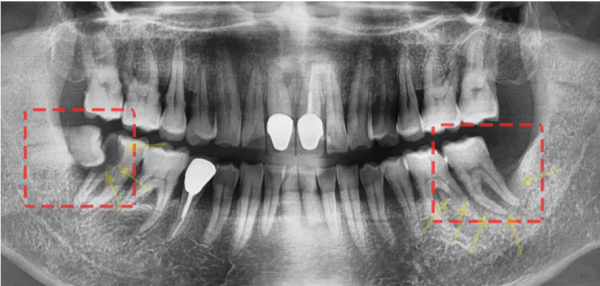

성남치과 더서울치과를 찾아주신, 이 환자분은 어금니의 통증으로인해 저희 치과를 찾아주셨습니다.

엑스레이를 보면, 양쪽 아래 어금니쪽이 문제가 있습니다.

한쪽은 사랑니때문에 충치가 생겨, 그 앞의 어금니가 거의 절반이 썩어있는 상태이고

사랑니가 없는쪽는 골 파괴 증상이 있어 염증이 가득 있습니다.

This patient, who visited Seongnam Dental Clinic The Seoul Dental Clinic, visited our dentist because of the pain in his molars.

If you look at the X-ray, there's a problem with both lower molars.

I have a cavity on one side because of my wisdom tooth, and almost half of the molars in front of me are rotten

The side without wisdom teeth has symptoms of bone destruction and is full of inflammation.